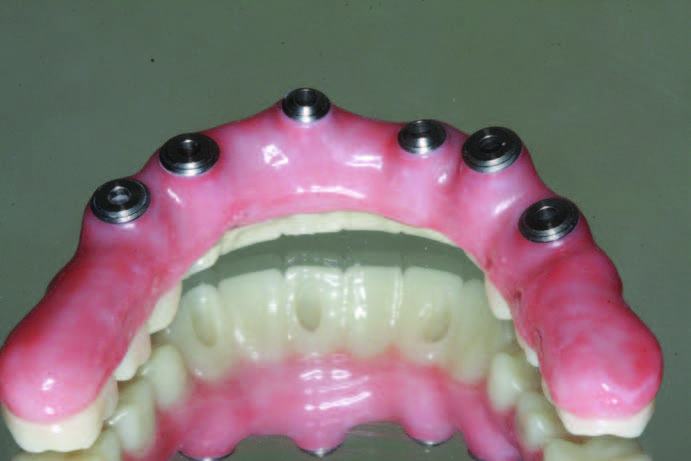

The ability to work out aesthetics and phonetics and test function prior to the finalization of prostheses cannot be understated. The final Obsidian fused-to-gold bridge (Glidewell Dental Laboratories) opposing a Monolithic BruxZir hybrid prosthesis mimics the prototypic restoration as confirmed with the PMMAs (Figure 18). The intaglio demonstrates the time, effort, and attention required to produce sluiceways that will facilitate the use of an oral irrigator and a proxy brush (Figure 19).

The retracted view and the patient’s full-face smile are demonstrative of the excellent laboratory communication and careful attention to each step in this patient’s journey (Figures 20 and 21). His oral care required extra attention due to his emotional and psychological deficits caused by his hydrocephaly. While dentists cannot guarantee the longevity of prostheses, the journey from this patient’s beginning to his new oral restorative beginning creates hope and changes interpersonal feelings and responsibility. The implant placement and number should allow for optimal mastication throughout his life with proper maintenance and homecare (Figure 22).